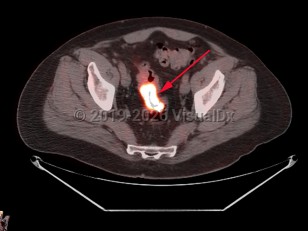

Rectal carcinomaRectal carcinoma

Metastatic pancreatic carcinomaMetastatic pancreatic carcinoma

EndometriosisEndometriosis

Ovarian cancerOvarian cancer